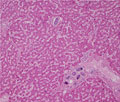

Macroscopic image: The liver is grossly normal and brownish in color.